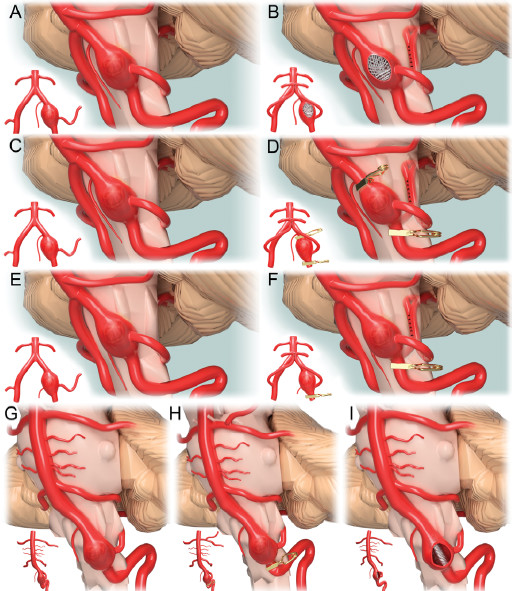

39. 累及小脑后下动脉和唯一脊髓前动脉起源的椎动脉梭形动脉瘤:病例报告与治疗模式提议

Fusiform vertebral artery aneurysms involving the posterior inferior cerebellar artery origin associated with the sole angiographic anterior spinal artery origin: technical case report and treatment paradigm proposal

Author: Kristine Ravina, Ben A. Strickland, Robert C. Rennert, Vance Fredrickson, Joshua Bakhsheshian, Mark Chien, William Mack, Arun Amar and Jonathan J. Russin

DOI: https://doi.org/10.3171/2018.5.JNS18681

涉及后小脑下动脉(PICA)的椎动脉(VA)梭形动脉瘤是罕见且具有挑战性的。脊髓前动脉(ASA)通常起源于单支椎动脉,开口于PICA远端。阻断单一开口的ASA可能导致双侧延髓内侧综合征。作者提出了一个基于ASA开口与梭形椎动脉瘤的距离来保留ASA的动脉瘤治疗模式,并分享了3代表性案例。在第一个病例中,他们首先行V3-PICA搭桥,然后椎动脉动脉瘤进行血管内栓塞术。动脉瘤和椎动脉完全闭塞同时也造成了ASA梗阻,造成不良结局。接下来的两个病例都是先接受PICA-PICA搭桥手术,随后进行血管内治疗闭塞椎动脉。两个病例均保留了远离动脉瘤的唯唯一ASA开口。ASA的解剖位置是累及PICA的梭形椎动脉瘤治疗方案选择的最关键因素。当ASA起源于动脉瘤,建议在有或无PICA搭桥的情况下行椎动脉近端闭塞。如果ASA远离动脉瘤,作者建议进行PICA搭桥,然后阻断动脉瘤载瘤动脉。而如果ASA紧邻动脉瘤,则应考虑行PICA搭桥和行动脉瘤孤立手术。

图:脊髓前动脉和动脉瘤的空间关系决定不同的治疗模式。